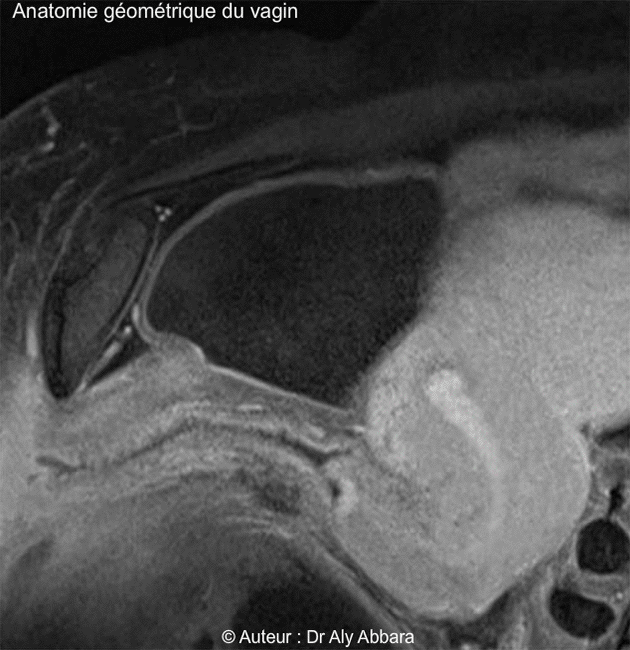

Petit pelvis - rapports anatomiques - Vagin - IRM

(Coupe sagittale médiane du pelvis - Imagerie par résonance magnétique - IRM).

• Morphologiquement le vagin est plus étroit au niveau de son tiers inférieur, près de la vulve, puis il s'élargit au niveau de son tiers moyen et surtout au tiers supérieur, cette étroitesse relative dans la portion vaginale située près de son entrée vulvaire est due à la présence des fuseaux musculaires des muscles releveurs de l'anus qui encerclent cette partie du vagin en arrière et bilatéralement. Cet encerclement musculaire donne au vagin une forme coudée ou arquée, donc en position décubitus dorsal, sur un plan sagittal médian, la partie basse du vagin est oblique (de l'arrière en bas vers l'avant en haut), la partie haute du vagin se dirige vers l'arrière. L'angle formé (ou l'arc) par les deux axes du vagin est un angle obtus, ouvert vers le bas (en position allongée sur le dos) et sa valeur est égale à environ à 140 degrés.

L'orifice externe du col utérin est posé sur la paroi postérieure du fond du vagin car l'axe du col est presque vertical sur la paroi vaginale postérieure.